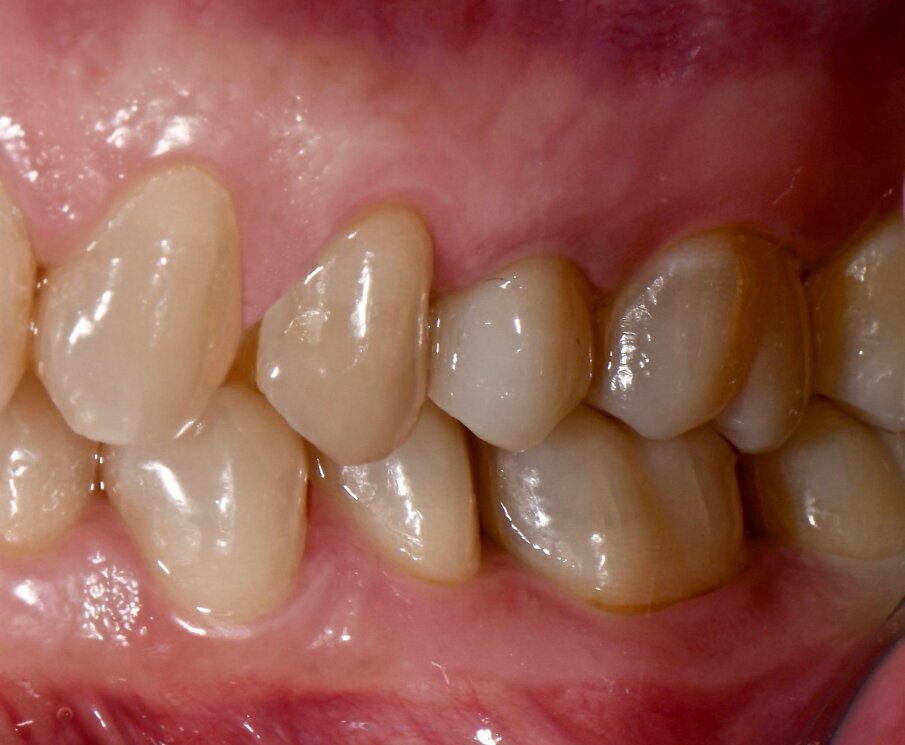

Materiali e metodi Case report Il presente case report è stato redatto in accordo con il CARE checklist (https://www.carestatement.org/checklist, consultato il 29 Gennaio 2024). Una paziente italiana di 44 anni, non fumatrice si è recata alla S.C Riabilitazione Orale Protesi Maxillo-Facciale e Implantologia Dentaria della Dental School dell’Università degli Studi di Torino nel mese di Gennaio 2023, lamentando sanguinamento gengivale durante lo spazzolamento. La paziente ha firmato un consenso informato. L’anamnesi medica della paziente non era rilevante. All’esame intraorale si evidenziava una scarsa igiene orale e la presenza di impianti in sito 15 e 25 (Figg. 1a-1c). I parametri parodontali al baseline sono stati riportati in Figura 2.

Fig. 1b - Condizione clinica al baseline: I e VI sestante.

Il Full Mouth Plaque Score (FMPS) era 71%, il Full Mouth Bleeding Score (FMBS) era 24% ed è stata osservata una profondità di sondaggio ≥ 4 mm nel 9,5% dei siti, localizzata a livello dei molari e premolari di entrambe le arcate. L’impianto in situ 15 (Nobel Replace, diametro 4,3mm, lunghezza 13mm) e l’impianto in situ 25 (Sweden & Martina SYRA, diametro 4,25 mm, lunghezza 1 mm) presentavano placca e una mucosa peri-implantare eritematosa ed edematosa. Per ciò che concerne l’impianto 15, si era riscontrata una moderata (PPD 4-5 mm) e severa (PPD≥ 6 mm) profondità di sondaggio, con una profondità media di 3.33 mm. FMBS e FMPS erano del 100%, così come riportato in Figura 2. La rilevazione dei parametri peri-implantari dell’impianto 25 aveva evidenziato PPD moderati nel 67% dei siti e una PPD severa a livello mesio-vestibolare. FMPS e FMBS erano 100%.